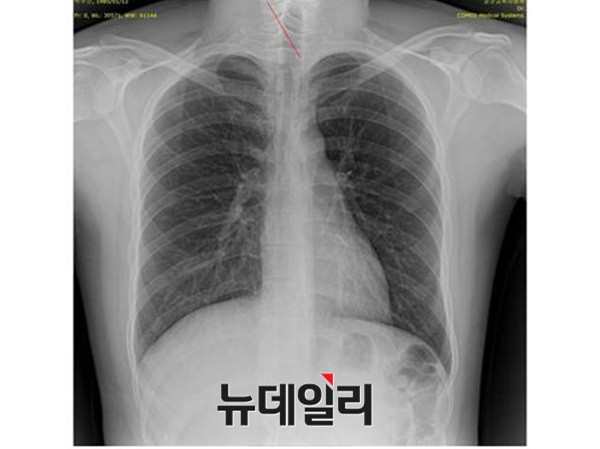

박주신씨의 신체를 촬영했다는 엑스레이는 모두 3개가 존재한다. 첫 번째는 2011년 12월 촬영된 자생병원 엑스레이이며, 두 번째는 박주신씨가 2011년 8월 공군에 입소하면서 본인 확인 후 촬영한 엑스레이다. 세 번째 엑스레이는 지난해 7월 주신씨가 영국 출국에 앞서 비자 발급을 위해 연세대 세브란스병원에서 새로 촬영한 것이다.

2011년 박주신씨에 대한 병역비리 의혹이 처음 불거진 뒤 지금까지 박주신씨의 신체를 촬영한 것으로 알려진 엑스레이는 모두 3개가 있다.이 가운데 언론을 통해 널리 알려진 자생병원 엑스레이(촬영일자 2011년 12월 9일)는, 박주신씨 본인이 아닌 제3자의 신체를 촬영한, 이른바 ‘대리신검자 엑스레이’라는 의심을 받고 있다.

- ▲ 박주신씨 명의의 자생병원 엑스레이. ⓒ 뉴데일리DB

반 면 지난해 12월부터 시작된 양승오 박사 등 시민 7명에 대한 공직선거법 위한 공판을 통해 새롭게 밝혀진, 박주신씨의 ‘공군훈련소 입소 당시 엑스레이’(촬영일자 2011년 8월 30일, 이하 공군 엑스레이)와, 주신씨가 ‘비자발급을 위해 촬영한 세브란스병원 엑스레이’(촬영일자 2014년 7월 31일, 이하 비자발급용 엑스레이)는 각각 박주신씨 본인의 신체를 촬영한 것으로 받아들여지고 있다.

- ▲ 박주신씨 공군훈련소 입소 당시 촬영된 엑스레이. ⓒ 뉴데일리DB

- ▲ 박주신씨가 지난해 7월 비자발급을 위해 촬영한 엑스레이. ⓒ 뉴데일리DB

이 들 세 개의 엑스레이는 모두 박주신씨의 신체를 촬영한 것으로 알려져 있기 때문에, 이들 엑스레이에 대한 판독결과 피사체를 동일인으로 볼 수 없는 유의미한 차이점이 발견된다면, 이는 박주신씨의 대리신검 혹은 영상자료 바꿔치기 의혹을 뒷받침하는 결정적 단서가 된다.

세 계적 권위를 인정받은 영상의학 전문의인 양승오 박사(동남권원자력의학원 암센터 핵의학과 주임과장)와 치과의사 김우현씨 등 박주신씨 병역비리 의혹을 주장해 온 시민들은, 위에서 언급한 세 개의 엑스레이에 대한 비교 판독 결과, 이들 엑스레이를 같은 사람의 것으로 볼 수 없는 차이점을 발견하고 이를 재판부에 증거자료로 제출했다.

‘석회화’와 ‘극상돌기’

‘석회화’란 나이가 들어 뼈에 발생하는 퇴행성 증상의 하나로 질병이라고 볼 수는 없지만 한 번 생기면 없어지지 않으며, X-Ray를 통해 확인할 수 있는 것으로 알려졌다.

- ▲ ▲박주신의 자생병원 X-Ray(왼쪽)과 공군 X-Ray(오른쪽). 자생병원의 엑스레이에서는 오른쪽 제1늑골부위에 '석회화'현상이 보이지만 공군엑스레이에선 보이지 않는다. ⓒ 뉴데일리DB

박주신씨의 자생병원 X-Ray를 보면, 오른쪽 제1 늑골부위에 ‘석회화’ 현상이 나타난다. 그러나 주신씨가 공군 입대 당시 찍은 X-Ray에는 이런 모습이 전혀 보이지 않는다.

이런 차이에 대해 양승오 박사의 변호인인 차기환 변호사 등은 "각각의 X-Ray를 찍은 사람이 동일인이 아니라는 것을 입증한다"고 설명했다.

‘극상돌기’의 경우에도 차이점은 명확히 드러난다.

변 호인 측은 “공군에서 찍은 엑스레이와 비자발급을 위해 찍은 엑스레이에서는 피사체의 제 1흉추 극상돌기가 오른쪽으로 휘어있지만, 자생병원에서 찍은 영상에서는 정방향으로 나온다”며, “박주신씨가 공군에 입대해 찍은 엑스레이와 세브란스 공개신검에서 나타난 피사체의 의학적 차이가 명확해 동일인이라고 인정할 수 없다”고 지적했다.

우리가 흔히 등을 만지면, 가운데 뾰족하게 솟아난 부분이 바로 ‘극상돌기’다.

흉추를 비롯해 모든 척추에 존재하며, 흉추에 외상이나 수술, 질병 등이 없었던 근접한 기간 동안 촬영된 엑스레이에서 극상돌기의 형태가 명확하게 다를 경우, 다른 개체라고 판단할 의학적 근거가 된다.